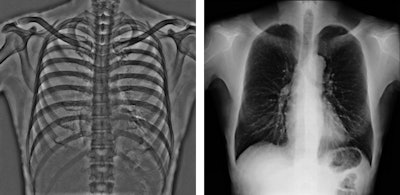

Image of a renal aneurysm acquired with Toshiba's Infinix-i Rite Edition digital radiography system."We focus on patient comfort, so our philosophy is to move neither the patient nor the table, but the hardware," noted René Degros, the company's European x-ray business unit manager.

As interventional procedures become more complex, advanced 3D acquisition is becoming increasingly important, he pointed out. There is also an emphasis on flexible, responsive technology, so the C-arm's lateral movement allows it to be moved out of the way during a procedure. During lung biopsies, for example, the unit can be flipped through 180ï‚° to place the flat-panel detector beneath the patient table.

The system is equipped with tableside controls to improve workflow. It also offers Toshiba's DoseRite package, which includes a range of tools developed to reduce radiation exposure for both clinicians and patients, including the Live Zoom, RiteSpot, and real-time dose-tracking features.